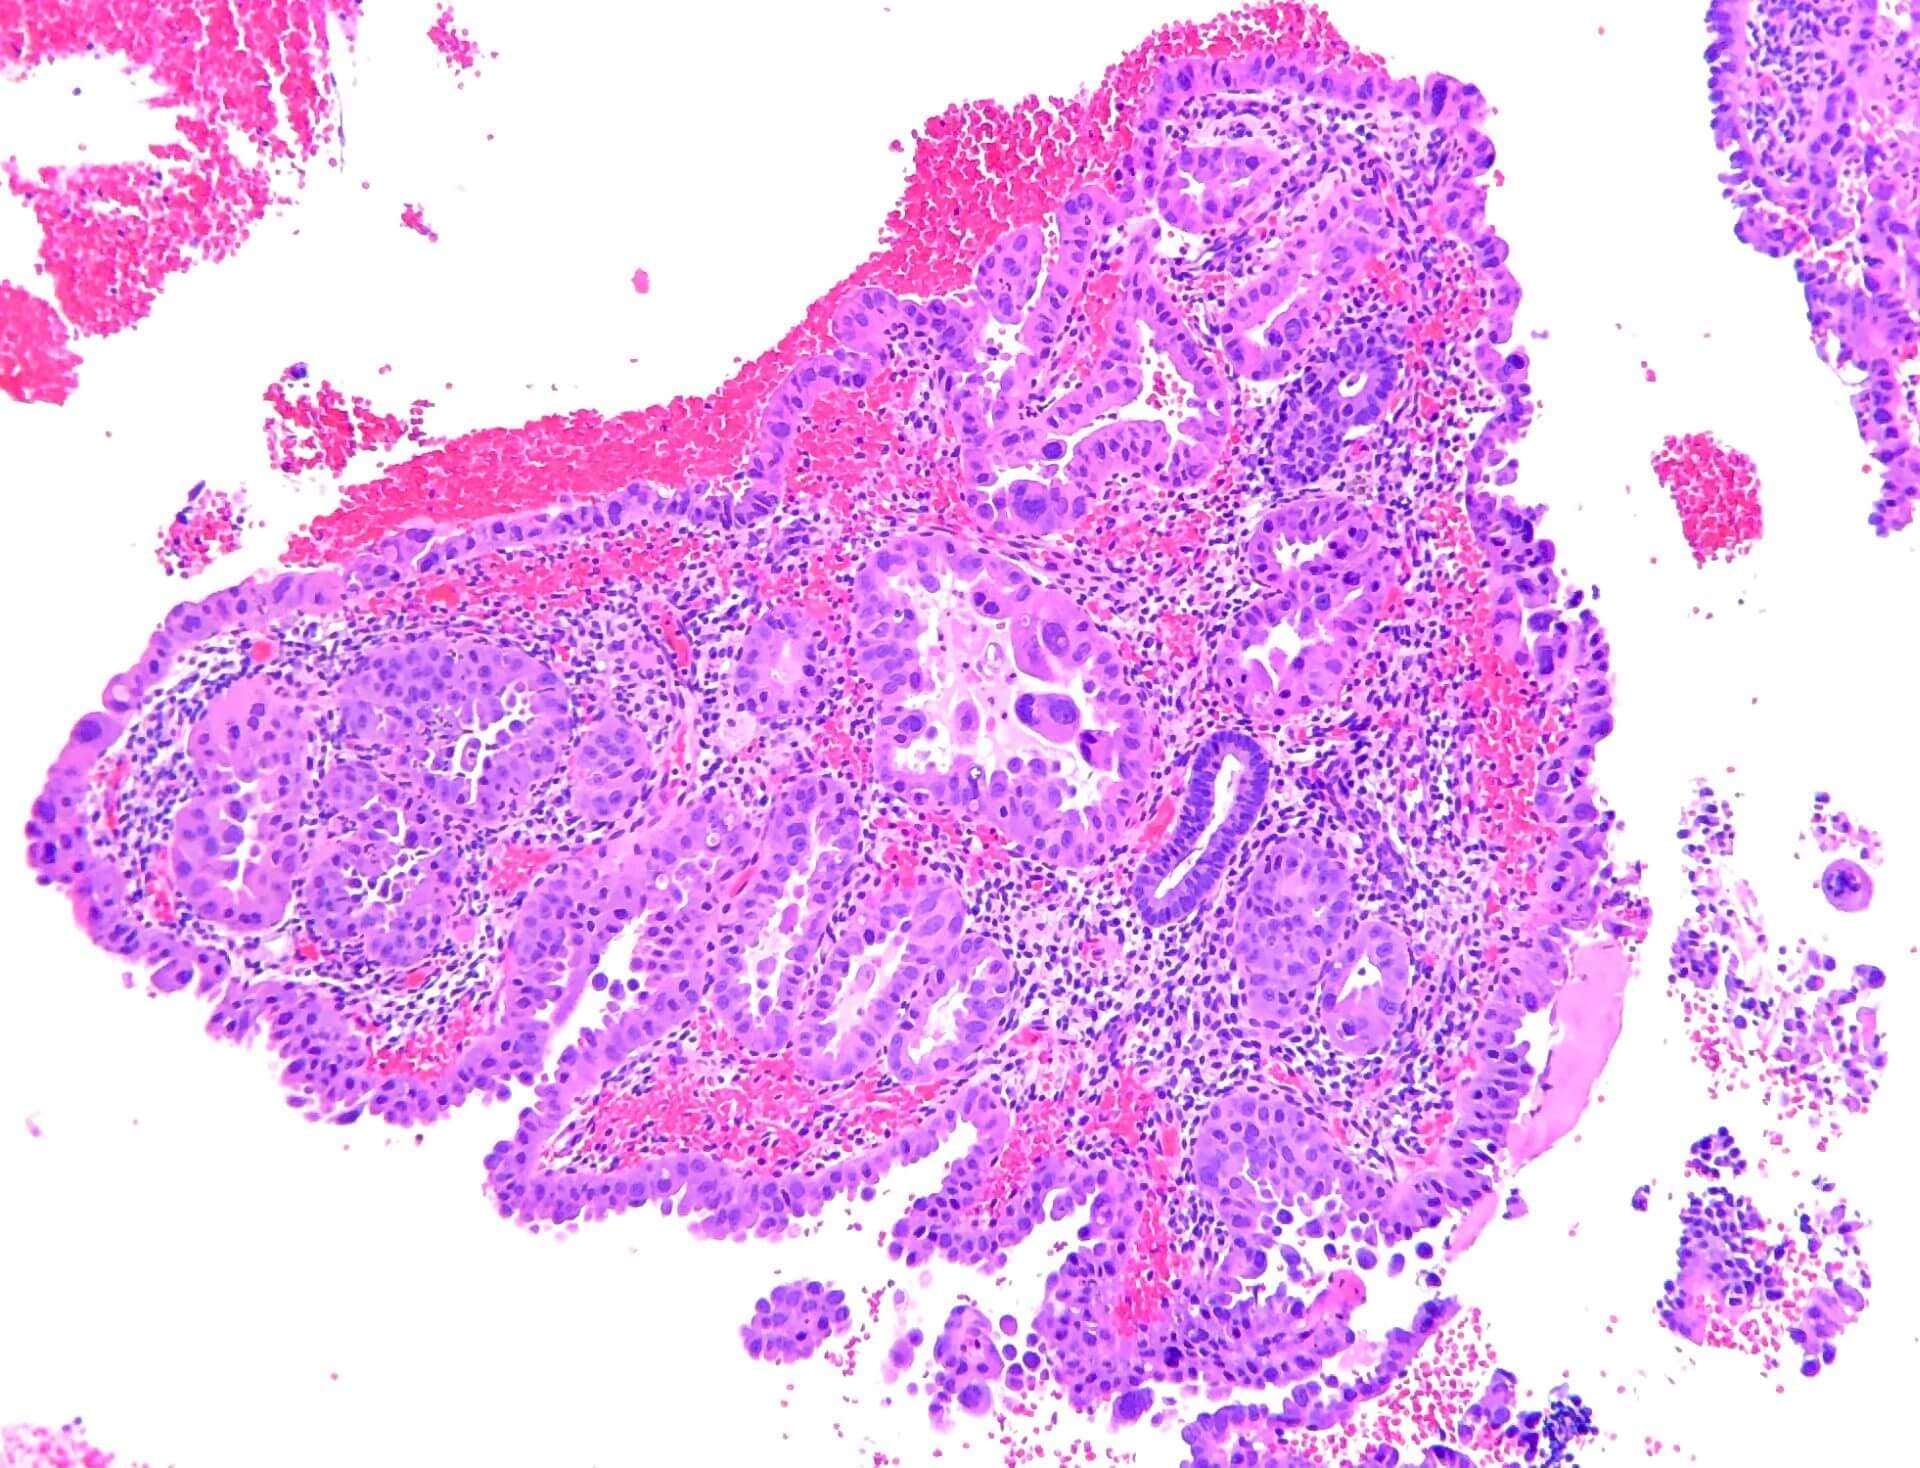

Klarzellige Karzinome und andere ungewöhnliche gynäkologische Tumore haben noch immer eine schlechte Prognose, erinnert Dr. Susana Banerjee, Institute of Cancer Research, London (1). Präklinische Untersuchungen hätten belegt, dass ATR-Inhibitoren selektiv Zellen mit ARID1A-Defekten abtöten können. Diese treten bei 30–40 Prozent der klarzelligen und endometroiden Karzinome auf. Ausserdem steigere die ATR-Hemmung die Zytotoxizität von PARP-Inhibitoren.

Die Referentin präsentierte nun die ersten Ergebnisse der ENGOT/GYN1/NCRI-ATARI-Studie für die jeweils ersten 29 Patientinnen aus allen drei Kohorten: die Forscher wendeten dabei den ATR-Inhibitor Ceralasertib gegen seltene gynäkologische Tumoren an. Teilnehmerinnen mit einem klarzelligen Karzinom und Verlust der ARID1A-Aktivität nahmen die Substanz als Monotherapie ein. Bei erhaltener Proteinfunktion kam ergänzend Olaparib zum Einsatz.